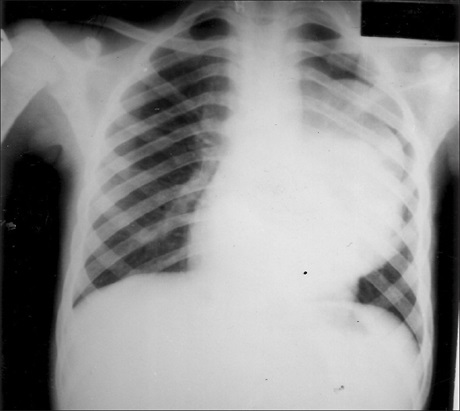

Dermatofibrosarcoma protuberans (DFSP) is a very rare, low-intermediate-grade sarcoma of the dermis layer of the skin; it has a marked propensity for local recurrence after excision. It is typically diagnosed during early adult life at a tumoral stage and it occurs rarely in children. This report is a case of childhood DFSP that had recurred five times within a period of eight years, each following surgical excision. This tumor also showed an uncommon myxoid change: Appearing as larger multi-nodular cutaneous plaque that arose at the site of excision of previous tumors some years earlier. The rarity of this tumor, and the fact that it is even rarer in children, prompted the report of this case.